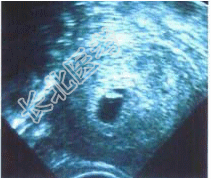

- 单项选择题38岁女性患者,已婚: 平素月经规则,周期30天, 现停经90余天,阴道少量流血10天。子宫腔内B超结果如图, 考虑( )

A、难免流产

B、稽留流产

C、子宫肌瘤

D、葡萄胎

E、先兆流产